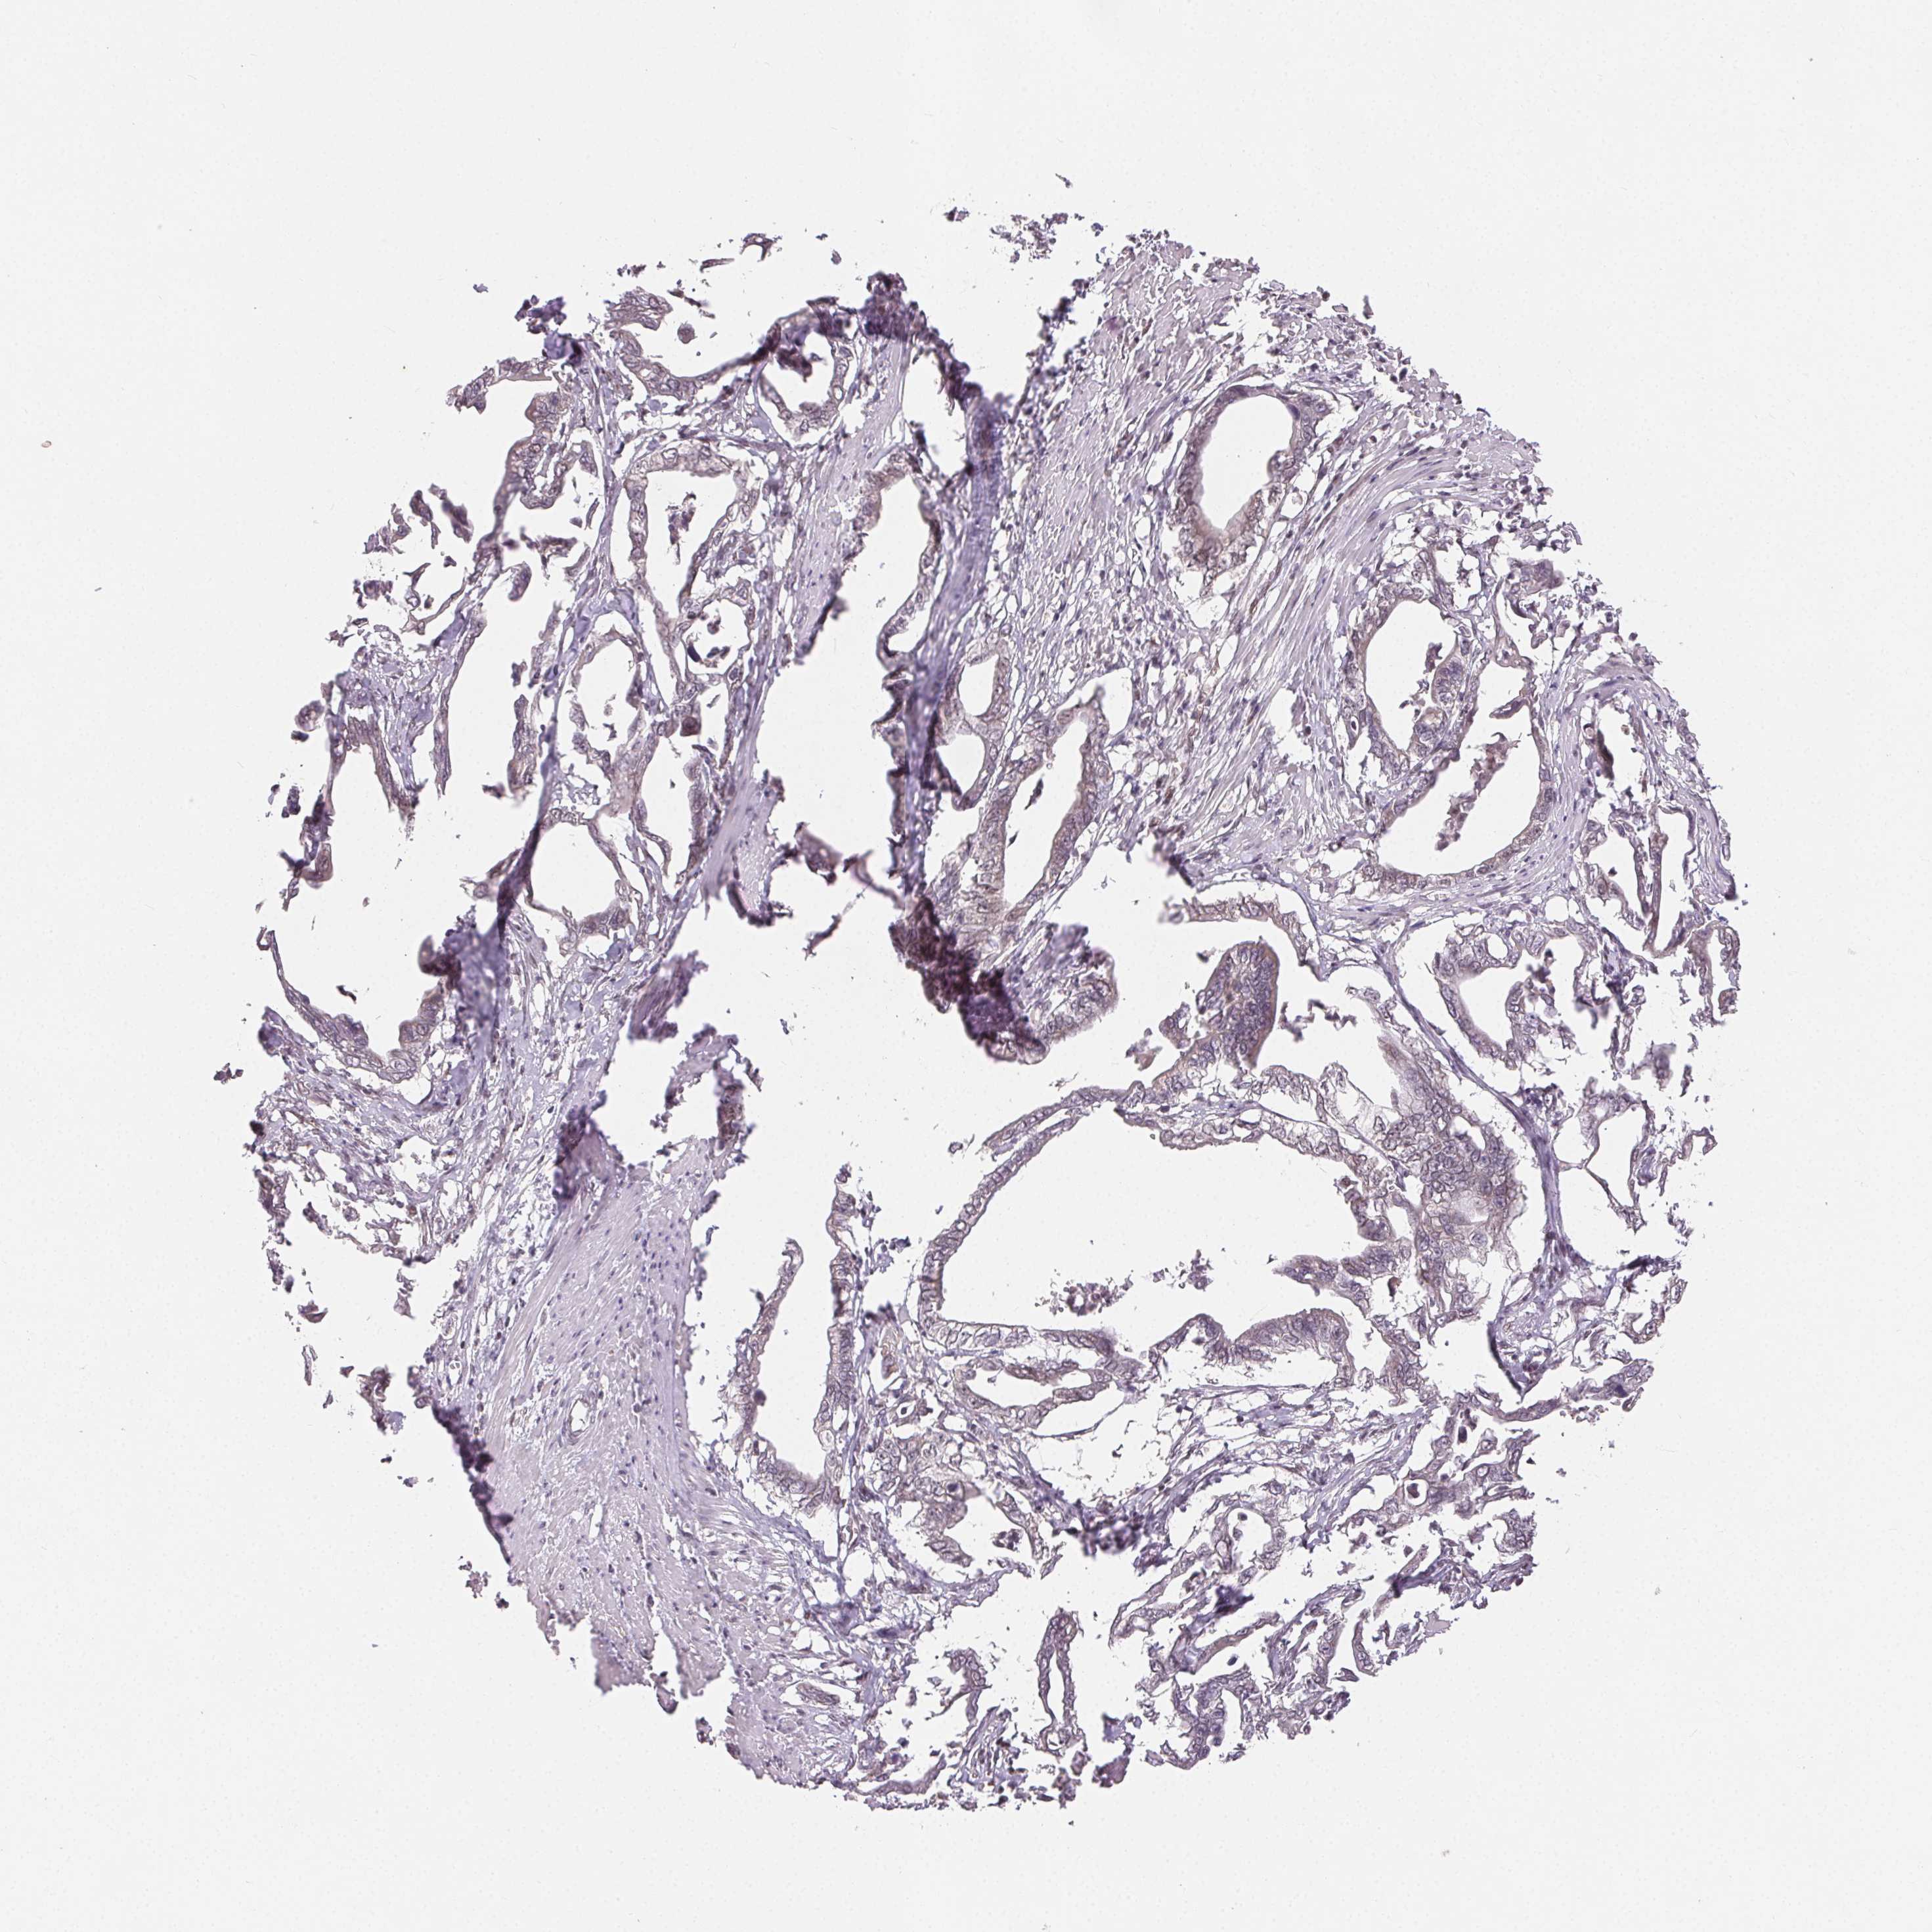

PANCREATIC CANCER - Protein expressioni

A mouse-over function shows sample information and annotation data. Click on an image to view it in a full screen mode. Samples can be filtered based on level of antibody staining by selecting one or several of the following categories: high, medium, low and not detected. The assay and annotation is described here.

Note that samples used for immunohistochemistry by the Human Protein Atlas do not correspond to samples in the TCGA dataset.

Antibody stainingi

Antibody staining in the annotated cell types in the current human tissue is reported as not detected, low, medium, or high, based on conventional immunohistochemistry profiling in selected tissues. This score is based on the combination of the staining intensity and fraction of stained cells.

Each image is clickable and will lead to virtual microscopy that enables deeper exploration of all samples and also displays staining intensity scores, fraction scores and subcellular localization as well as patient and tissue information for each sample.

Antibody HPA063708

Antibody HPA064435

Antibody CAB010297

Staining

High

Medium

Low

Not detected

Intensity

Strong

Moderate

Weak

Negative

Quantity

>75%

75%-25%

<25%

None

Location

Nuclear

Cytoplasmic/membranous

Cytoplasmic/membranous,nuclear

Adenocarcinoma, NOS

Adenocarcinoma, metastatic, NOS